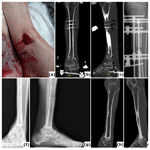

Figure 4Chronic infection (osteomyelitis) following extended external fixation. (a) Clinical image presenting a fistula with purulent fluid drainage in a 64-year-old patient after multiple surgical procedures for fracture-related infection (FRI) of the proximal tibia with non-union. (b) Anteroposterior radiograph of the tibia showing consolidation of the proximal tibia fracture; the external fixation time (EFT) was 16 months. (c) Clinical image depicting a chronic wound on the posterior aspect of the ankle in a 54-year-old patient after several surgical interventions for FRI of the distal tibia. Bone transport was performed as treatment, with an EFT of 12 months. At referral, the patient had local and systemic signs of infection and was prescribed oral antibiotics. These episodes have recurred intermittently over 3 years following removal of the external fixator. (d) Anteroposterior radiograph of the tibia demonstrating consolidation at all sites.